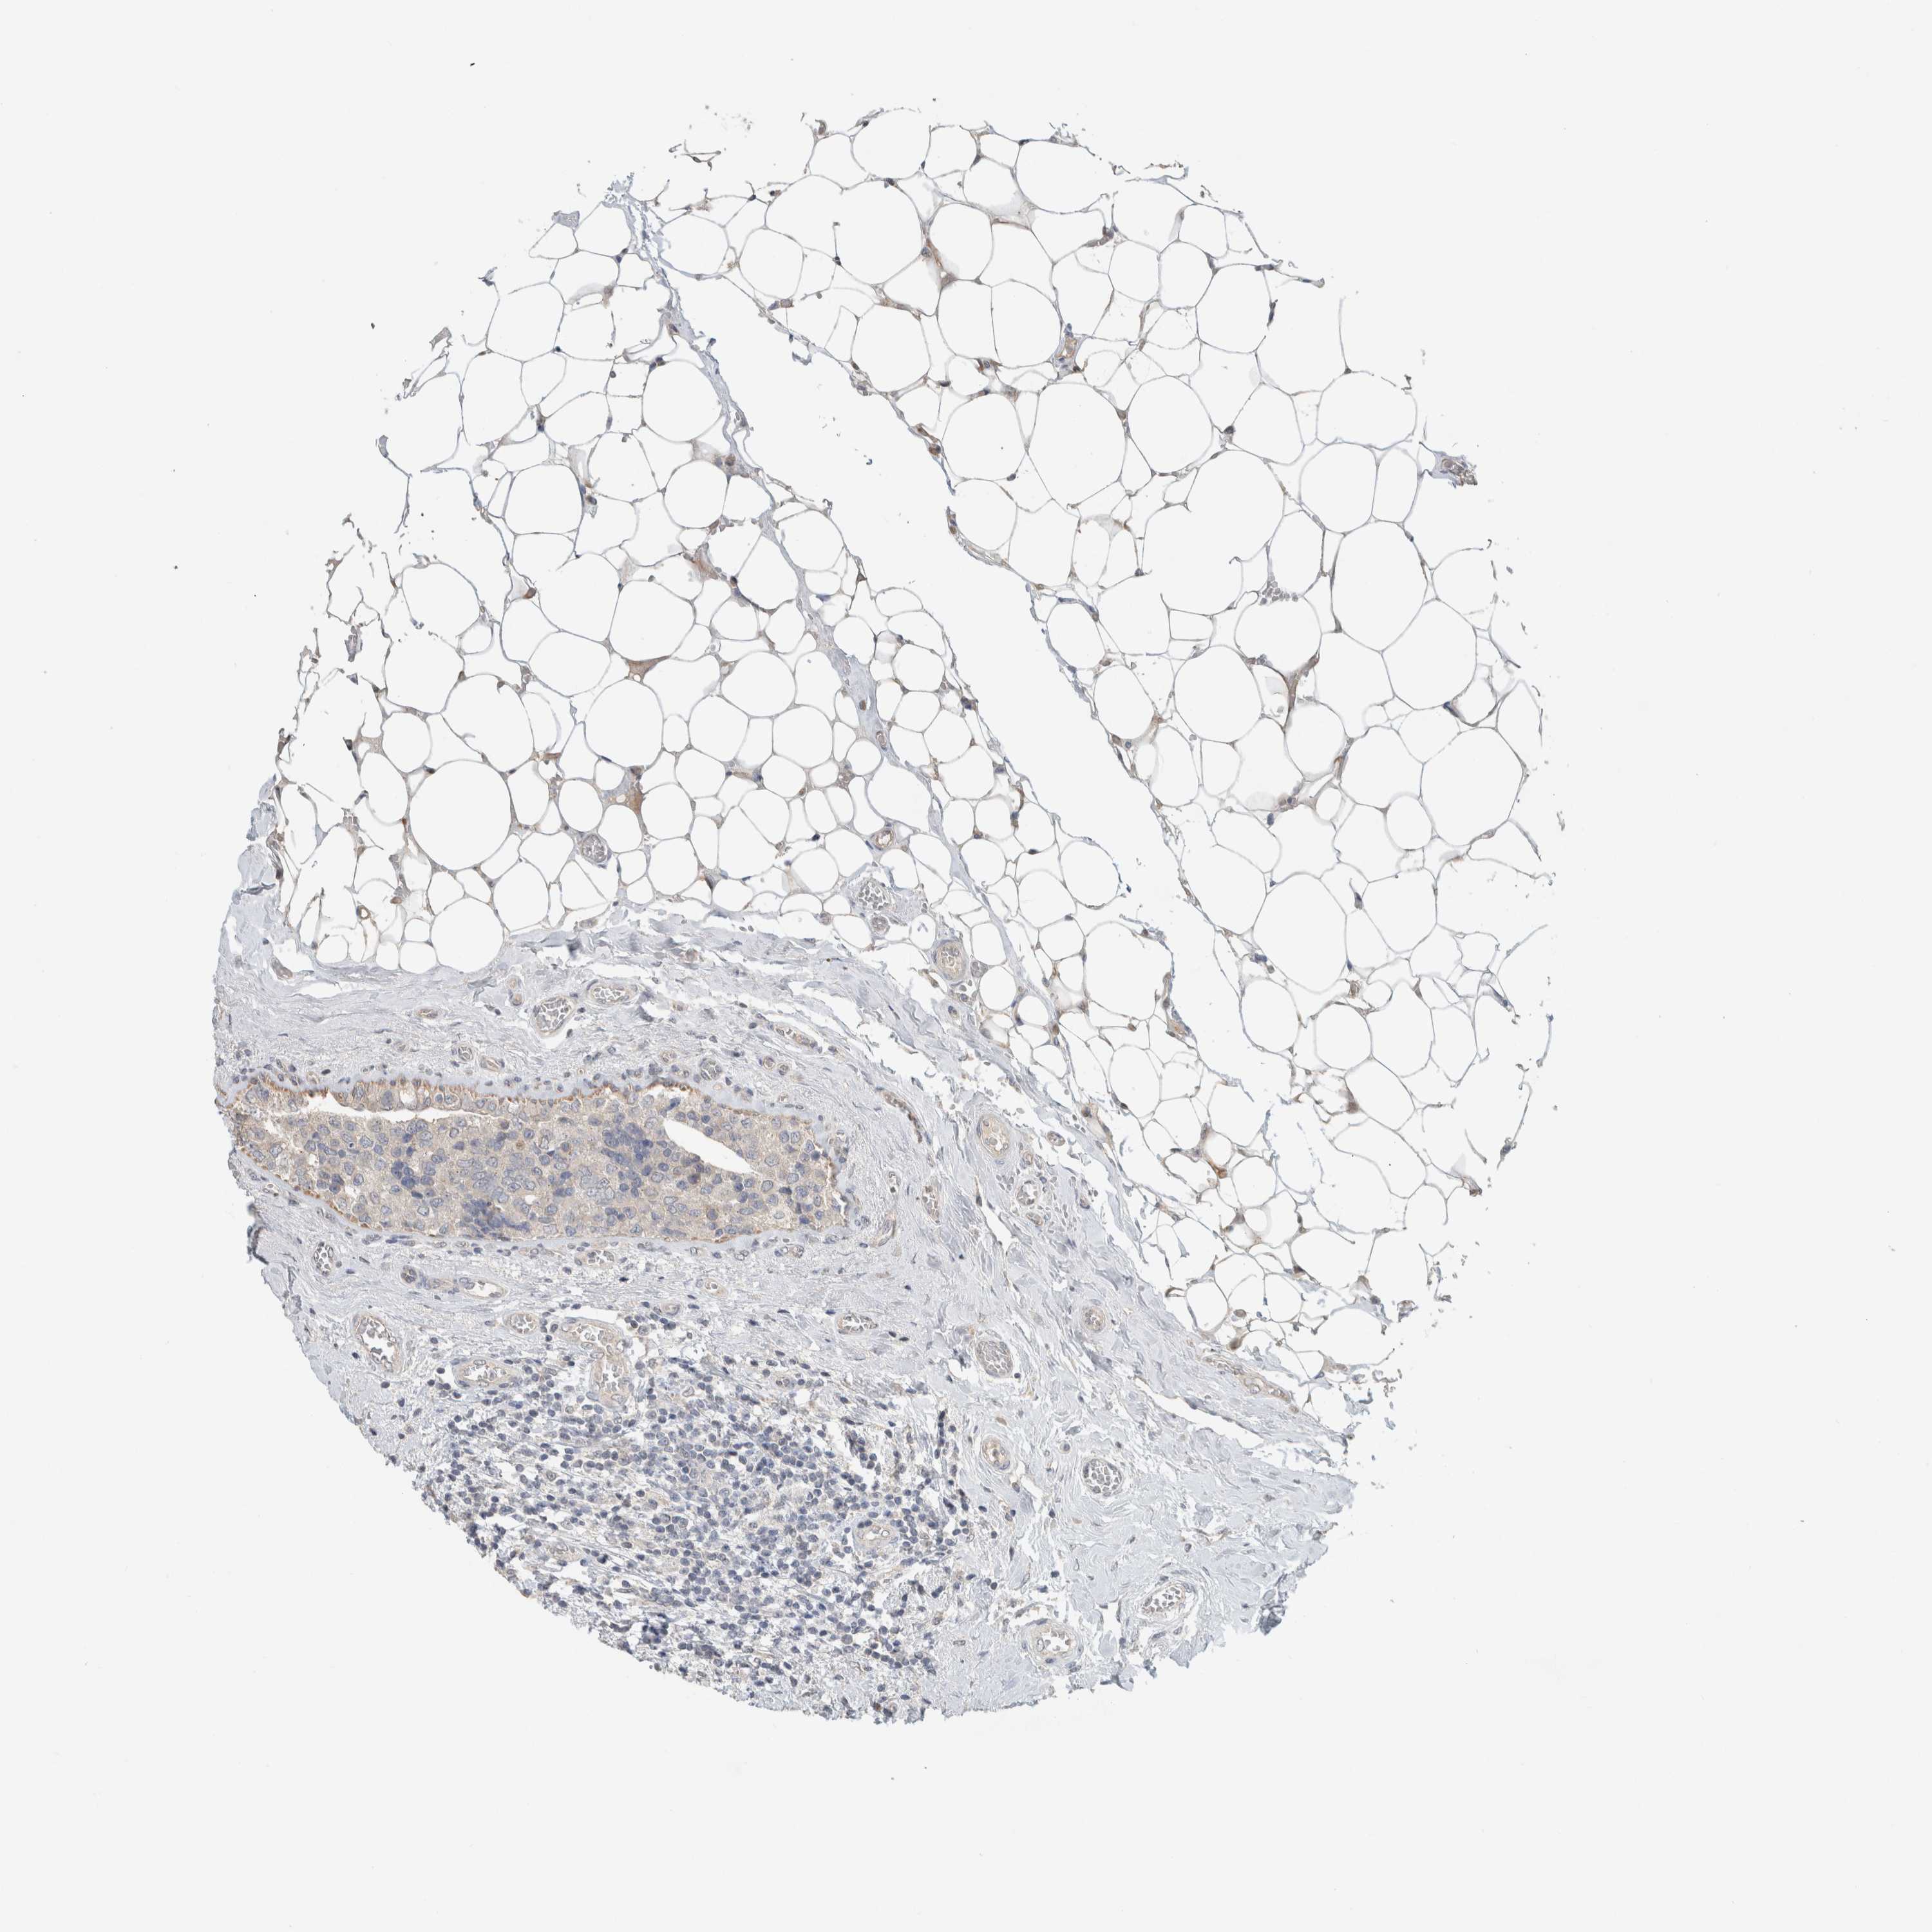

BRCA TCGA BRCA VALIDATION PROTEIN EXPRESSION

ANTIBODIES

AND

VALIDATION